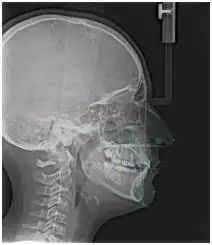

5 正畸X光片

(又叫侧位X光片或头影测量片)

这种X光片显示头颅侧面,用来评估颌骨生长和头骨间关系。帮助正畸医生做出精确的诊断,制定出一份治疗方案。